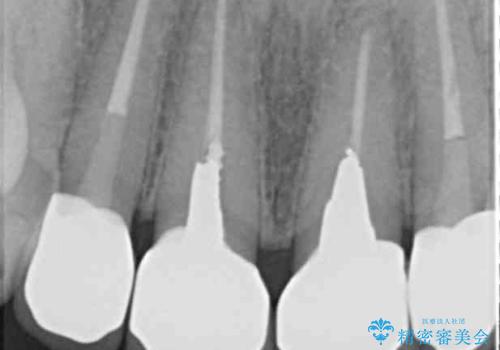

- 「黒ずみの前立つ前歯をやりかえ、きれいにしたい。」と希望され来院されました。

金属色の目立つ前装冠を除去し、発生していた小さな虫歯を丁寧に全て除去しジルコニアセラミッククラウンで審美的な前歯となるような治療を計画します。